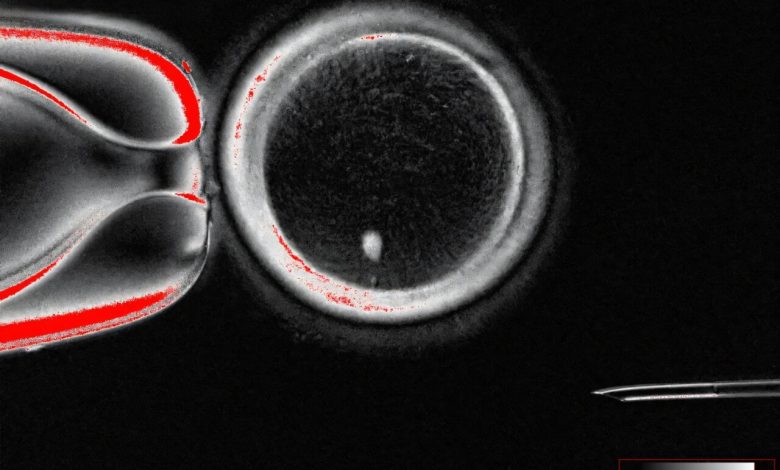

Pesquisadores da OHSU demonstraram uma nova técnica para tratar a infertilidade, transformando as células da pele em oócitos ou ovos. Mostrado aqui, uma imagem de um oócito com uma imagem brilhante de um núcleo de células da pele antes da fertilização. Crédito: Universidade de Saúde e Ciências do Oregon

- Os pesquisadores transplantam o núcleo de uma célula da pele em um ovo, ou oócito, despojado de seu próprio núcleo.

- Promovido pelo citoplasma dentro do ovo de doador, o núcleo das células da pele implantado descarta idealmente metade de seus cromossomos em um processo semelhante à meiose. Esta é a etapa chave, resultando em um ovo haplóide com um único conjunto de 23 cromossomos em vez de 46.